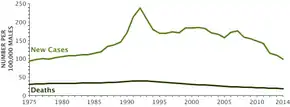

Many cases are managed with active surveillance or watchful waiting.[3] Other treatments may include a combination of surgery, radiation therapy, hormone therapy or chemotherapy.[3] When it only occurs inside the prostate, it may be curable.[2] In those in whom the disease has spread to the bones, pain medications, bisphosphonates and targeted therapy, among others, may be useful.[3] Outcomes depend on a person's age and other health problems as well as how aggressive and extensive the cancer is.[3] Most men with prostate cancer do not end up dying from the disease.[3] The 5-year survival rate in the United States is 98%.[5] Globally, it is the second most common type of cancer and the fifth leading cause of cancer-related death in men.[18] In 2018, it occurred in 1.2 million men and caused 359,000 deaths.[6] It was the most common cancer in males in 84 countries,[4] occurring more commonly in the developed world.[19] Rates have been increasing in the developing world.[19] Detection increased significantly in the 1980s and 1990s in many areas due to increased PSA testing.[4] Studies of males who died from unrelated causes have found prostate cancer in 30% to 70% of those over age 60.[2]

In 2018, an estimated 164,690 new cases and 29,430 prostate cancer–related deaths will occur in the United States. Prostate cancer is now the second-leading cause of cancer death in men, exceeded by lung cancer and colorectal cancer. It accounts for 19% of all male cancers and 9% of male cancer-related deaths. Age-adjusted incidence rates increased steadily from 1975 through 1992, with particularly dramatic increases associated with the inception of widespread use of prostate-specific antigen (PSA) screening in the late 1980s and early 1990s, followed by a fall in incidence. A decline in early-stage prostate cancer incidence rates from 2011 to 2012 (19%) in men aged 50 years and older persisted through 2013 (6%).

Between 2013 and 2015, mortality rates appear to have stabilized. Declines in mortality rates in certain jurisdictions may reflect the benefit of PSA screening, but these observations may be explained by independent phenomena such as improved treatments. The estimated lifetime risk of a prostate cancer diagnosis is about 14.0%, and the lifetime risk of dying from this disease is 2.6%. Cancer statistics from the American Cancer Society and the National Cancer Institute indicated that between 2005 and 2011, the proportion of disease diagnosed at a locoregional stage was 93% for whites and 92% for African Americans; the proportion of disease diagnosed at a late stage was 4% for whites and 5% for African Americans.